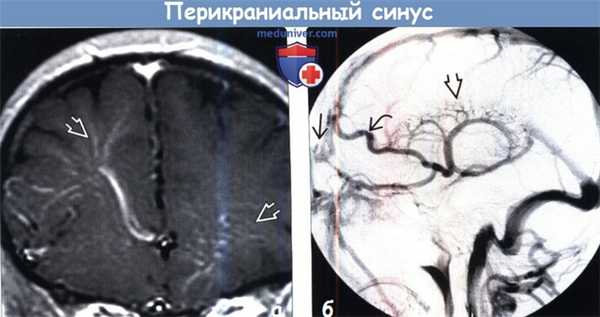

(а) КТ-венография, сагиттальная реформация: у того же пациента наглядно определяется варикозно расширенное венозное образование в мягких тканях головы, сообщающееся через дефект костей свода черепа с подлежащим ВСС.

(б) ЦСА, поздняя венозная фаза: у другого пациента определяется варикозно расширенное венозное образование, сообщающееся с ВСС через крошечную чрескостную вену. Здесь представлен добавочный тип перикраниального синуса (ПС).

2. КТ при перикраниальном синусе:

• Бесконтрастная КТ:

о Объемное образование в мягких тканях головы мягкотканной плотности:

- Септальные перегородки, кисты, флеболиты наблюдаются редко (как правило, при ВМ)

о Костное окно:

- Один/несколько четко очерченный(х) дефект(ов) кости

- Эрозия от давления, оказываемого вышележащей варикозно расширенной веной/ВМ

• КТ с контрастированием:

о Интенсивное хорошо очерченное контрастирование:

- Гетерогенное контрастирование при наличии тромба или ВМ

• КТ-венография: лучший метод визуализации компонентов сосудов

5. Ангиография:

• Визуализация связи между СТМО и экстракраниальными венами в венозную фазу